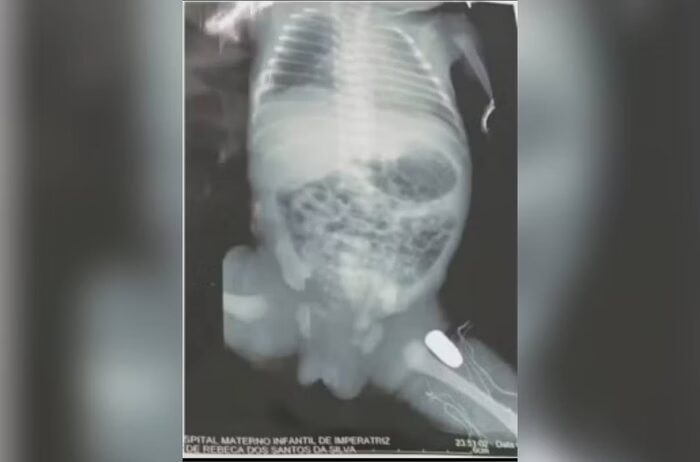

Segundo a Polícia Militar do Maranhão (PMMA), a adolescente caminhava na rua com companheiro quando dois foram baleados. O casal foi socorrido e a jovem teve que passar por cesárea. Exames de raio-x apontaram que a bala ficou alojada na perna do bebê.

De acordo com a Secretaria de Estado de Saúde (SES), o estado de saúde da vítima é estável e o bebê deve ser operado ainda nesta segunda-feira, 17, para retirar o projétil.